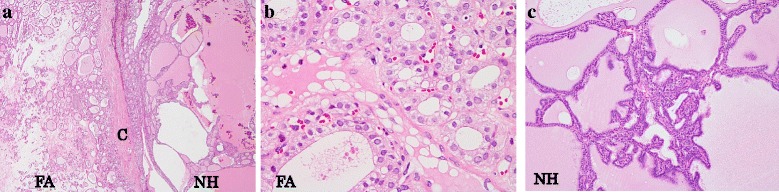

Fig. 4.

Histology of the thyroid gland. a Multiple follicular adenomas with a thick fibrous capsule were found in the bilateral lobes. Nodular hyperplasia was scattered in the background of the follicular adenomas (H & E stain x2 objective, FA: follicular adenoma, NH: nodular hyperplasia, C: capsule). b Most follicular adenomas had the characteristics of the oxyphilic cell variant (H & E stain x40 objective). c Nodular hyperplasia had colloid-filled follicles of variable size. It also had collections of small follicles projecting into the lumen of large actively secreting follicles (Sanderson pollsters) (H & E stain; x10 objective ). There was no evidence of malignancy and lymph nodes were normal